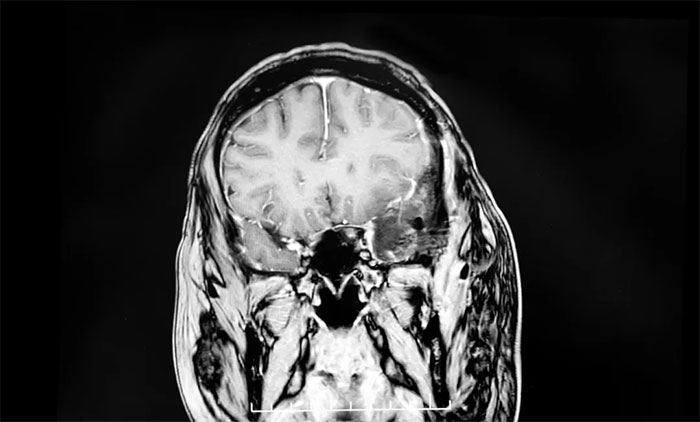

一天,李大哥從工位上起身,突然感到一陣頭暈眼花,他趕緊站定緩了一緩,頭暈的勁兒很快就過去了,李大哥也就沒太放在心上?蓻]想到,頭暈的癥狀漸漸頻繁了起來,持續(xù)了一個多月還未見好。李大哥心下有些不安,決定去醫(yī)院做個檢查,最終查出巨大腦膜瘤。

為何腦膜瘤發(fā)現時常常很大?上海藍十字腦科醫(yī)院【同濟大學附屬藍十字腦科醫(yī)院(籌)】6B神經外二科副主任盧云鶴博士解釋:腦膜瘤多為顱內良性腫瘤,生長緩慢。尤其在“神經功能啞區(qū)”(對早期癥狀不敏感的區(qū)域),患者在早期幾乎沒有明顯不適。只有當腫瘤長到一定程度,壓迫周圍組織或血管,影響大腦功能時,才會出現較明顯的癥狀。一旦癥狀顯現,往往意味著腫瘤已無生長空間,隨時可能誘發(fā)腦疝甚至呼吸心跳驟停等致命危險,必須盡快手術。

▲ 腦膜瘤早期癥狀較為隱匿